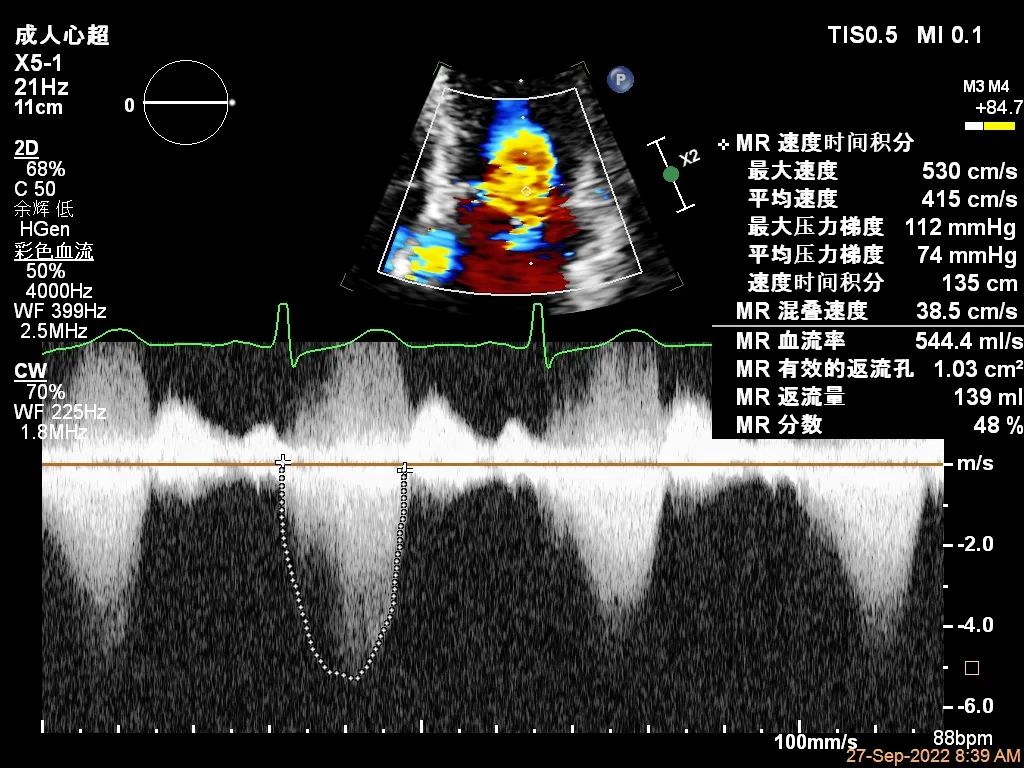

“贞”心一“课”|TEER成功治疗外交界隆起合并P3区宽大Flail病变一例